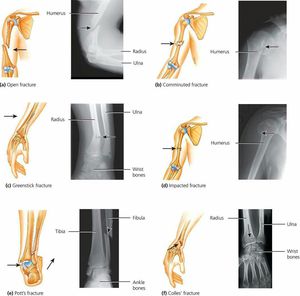

Common types of bone fractures